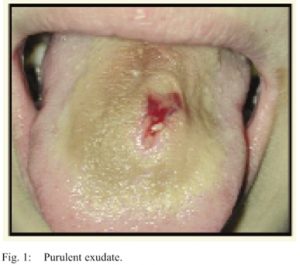

Primarily, oral piercings are made of metal, and therefore can cause inconvenience in dental treatment and examinations, especially regarding the taking of x-rays. This metal can also cause abrasion, wearing, chipping and sometimes even breakages in the teeth, which is not easily rectifiable. This can also lead to an increase in tooth sensitivity, which can be extremely painful and prevent individuals from enjoying their food. Our mouths are always moving, and this means the piercing is moving too, rubbing against many different surfaces in the mouth. The constant rubbing action of lip or tongue piercings against the gums can lead to gum recession, where the gums shrink back to protect against the relentless rubbing, which leaves tooth surface exposed to potential acid erosion, which can lead to sensitivity, decay and even tooth loss! Not to mention, poor oral hygiene concerning a tongue piercing can give you awful bad breath, not pleasant for anybody!